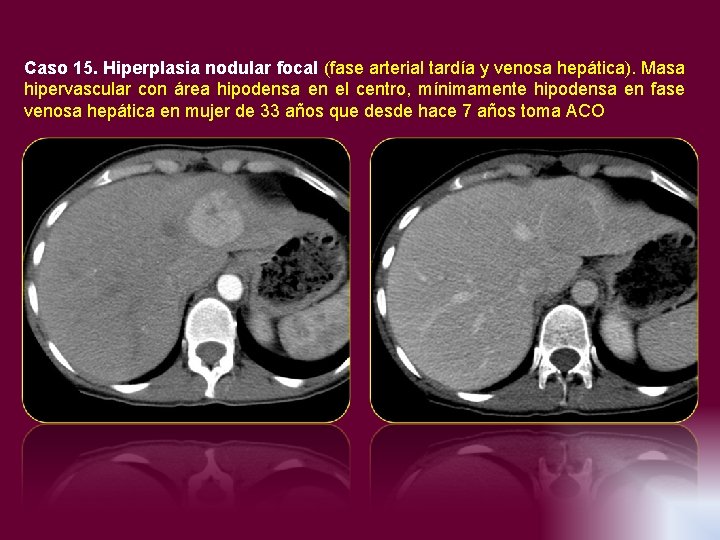

Caso 15. Hiperplasia nodular focal (fase arterial tardía y venosa hepática). Masa hipervascular con

Caso 15. Hiperplasia nodular focal (fase arterial tardía y venosa hepática). Masa hipervascular con área hipodensa en el centro, mínimamente hipodensa en fase venosa hepática en mujer de 33 años que desde hace 7 años toma ACO